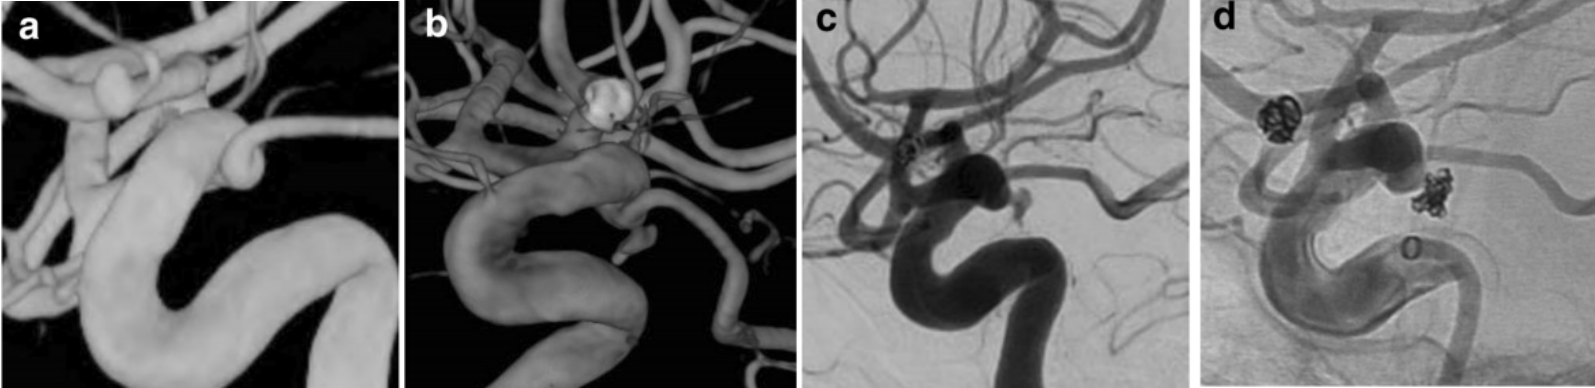

图2. 76岁老年女性患者。a.2004年因蛛网膜下腔出血行右侧大脑前动脉瘤栓塞术,术中发现右侧后交通膨大.随访超过十年未见明显异常。b,c.患者再次蛛网膜下腔出血,造影提示后交通膨大新发动脉瘤,大脑前动脉瘤稳定。d.单纯弹簧圈栓塞动脉瘤,后交通动脉保护良好。